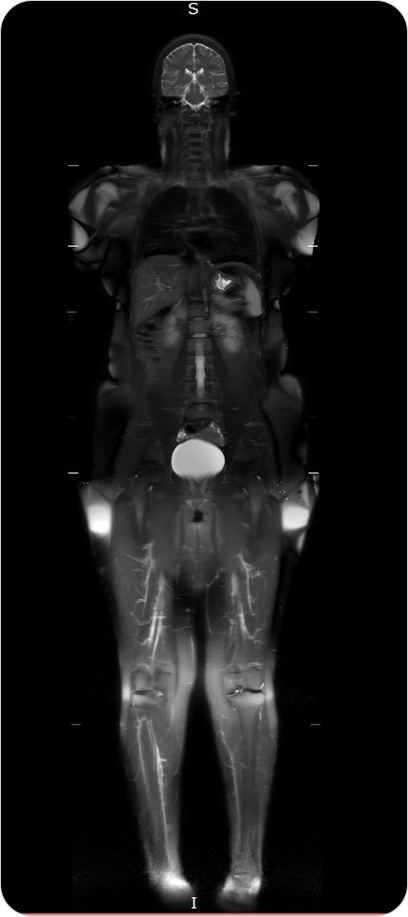

Resonancia Magnética Total

La resonancia de cuerpo entero permite examinar de forma integral todos los órganos y sistemas, sin utilizar radiación, siendo ideal para chequeos médicos preventivos y evaluación de enfermedades sistémicas.

Es un estudio no invasivo que permite visualizar de manera integral el cuerpo humano, sin radiación. Ofrece imágenes de alta resolución de órganos, tejidos blandos, sistema musculoesquelético y más.

¿PARA QUE SE UTILIZA?

- Detección precoz de tumores, lesiones o inflamaciones en órganos.

Seguimiento de pacientes oncológicos. - Evaluación del estado general de salud en chequeos preventivos.

Estudio de enfermedades musculares, articulares o neurológicas que afectan varias zonas del cuerpo. - Detección de metástasis o lesiones ocultas.

¿POR QUÉ ES UN ESTUDIO DESTACADO?

- Cobertura completa del cuerpo en una sola sesión.

- Sin uso de radiación.

- Alta sensibilidad para detectar lesiones incluso cuando son pequeñas.

- Muy útil en chequeos médicos de prevención de enfermedades graves.

Resonancia Magnética Total

La resonancia de cuerpo entero permite examinar de forma integral todos los órganos y sistemas, sin utilizar radiación, siendo ideal para chequeos médicos preventivos y evaluación de enfermedades sistémicas.

Es un estudio no invasivo que permite visualizar de manera integral el cuerpo humano, sin radiación. Ofrece imágenes de alta resolución de órganos, tejidos blandos, sistema musculoesquelético y más.

¿PARA QUE SE UTILIZA?

- Detección precoz de tumores, lesiones o inflamaciones en órganos.

Seguimiento de pacientes oncológicos. - Evaluación del estado general de salud en chequeos preventivos.

Estudio de enfermedades musculares, articulares o neurológicas que afectan varias zonas del cuerpo. - Detección de metástasis o lesiones ocultas.

¿POR QUÉ ES UN ESTUDIO DESTACADO?

- Cobertura completa del cuerpo en una sola sesión.

- Sin uso de radiación.

- Alta sensibilidad para detectar lesiones incluso cuando son pequeñas.

- Muy útil en chequeos médicos de prevención de enfermedades graves.